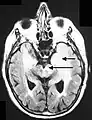

Axial fluid-attenuated inversion recovery MRI image demonstrating tumor-related infiltration involving lenticular nuclei (Arrow).